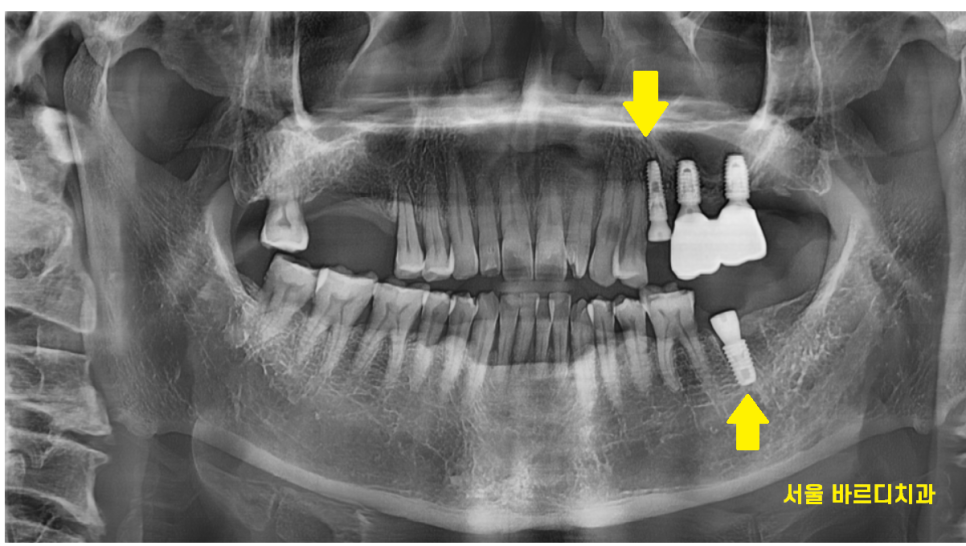

오른쪽 위에 부분은 발치 된지 오래된 상태

치아가 없어서 주로 왼쪽으로 식사를 하다보니

왼쪽이 불편하다고 하셨습니다.

24.02.27

강일동 치과에서는 환자분이 멀리서 오셨기에

발치 후 당일 임플란트 수술을 진행해드릴 수 있다

설명드렸는데요.

오른쪽은 치아 상실

왼쪽은 통증

치과 치료의 우선순위에 있어

통증 해결이 1순위라

문제 치아를 뽑고

발치 후 당일 임플란트 수술 완료해드렸습니다.